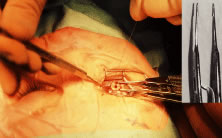

The globe then is gently elevated from the orbit or proptosed at the same time it is abducted or adducted to prepare for the incision. Elevation of the globe helps to separate the horizontal rectus muscle from the inferior rectus muscle so that the inferior rectus muscle is not cut when the incisions are made. The conjunctiva is grasped by the assistant with a Manhattan toothed forceps (Fig. 10). This forceps has teeth that are angled outward and are designed to grasp conjunctiva, as well as the deeper subconjunctival tissue, so that when the blunt-tipped Westcott scissors cuts into the tented tissue, an incision is made into the conjunctiva and Tenon's capsule (Fig. 11A and B). If the incision does not completely penetrate Tenon's capsule and the intermuscular septum to the scleral surface of the eye, additional tissue (anterior Tenon's tissue and/or intermuscular septum) is grasped with the Manhattan forceps and at least one additional cut is made.

A Stevens' tenotomy hook is passed by the surgeon into the incision and is rotated so that it can be slid underneath the muscle insertion with the tip of the hook held tangential to the globe (Fig. 12). The hook should be passed 2 to 3 mm posterior to the expected location of the muscle insertion. Care is taken not to incorporate intramuscular septum or other adventitial tissue on the hook. When the lateral rectus muscle is secured with the Stevens' or Jameson muscle hook, care should be taken not to bring the inferior oblique muscle up to the insertion (Fig. 13). When the muscle is secured with the Stevens' hook, the hook and the inferior edge of the muscle insertion are elevated and a Jameson muscle hook is passed between the tented muscle tissue and the sclera to secure the muscle at its insertion (Fig. 14). Care is taken to include the entire insertion of the tendon on the hook. The tip of the Jameson hook is gently elevated by depressing the heel of the hook. This maneuver helps to ensure that the entire tendon of the muscle remains captured on the hook. A Stevens' tenotomy hook is placed in the incision, this time anterior to the insertion beneath the conjunctiva (Fig. 15). The Stevens' hook is passed posterior over the orbital surface of the muscle (Fig. 16). Gentle pressure on the Stevens' hook is directed posterior so that the check ligaments and Tenon's tissue that overlie the muscle belly are separated from the muscle capsule with blunt dissection. The hook usually is passed posterior for about 10 mm. When recessing a lateral rectus, attachments between the underside of the lateral rectus and inferior oblique are broken (Fig. 17). Two or three passes over the muscle are made, and, with simultaneous countertraction on the Stevens' hook and the Jameson hook, the conjunctiva is elevated and pulled over the tip of the Jameson hook (Fig. 18A and B).